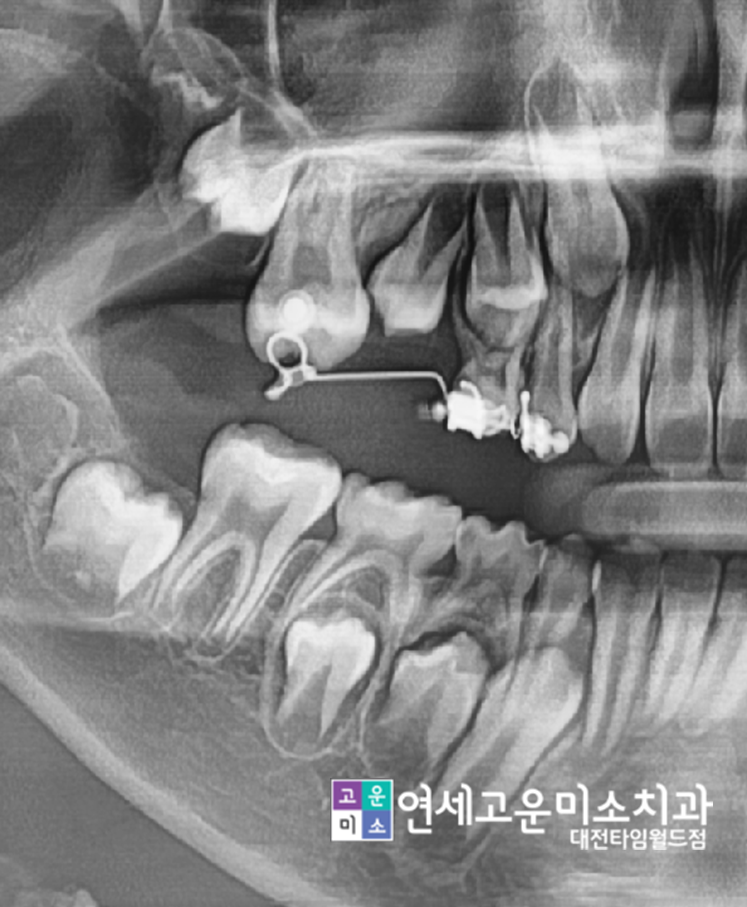

Case 3. 영구치 맹출장애

"이가 안 나와요"

위에 동그라미 친 부위를 보면 큰 어금니 맹출 방향이

앞쪽으로 맹출 되어 유치에 걸려서 못 나오고 있습니다.

이렇게 되면 큰 어금니 또 못 나올 뿐 아니라

작은 어금니 나올 공간도 없어지게 됩니다.

치아 배열의 문제는 원칙적으로는

영구치가 모두 나온 이후에 하는 것이 맞지만

이처럼 공간 부족 문제가 심각한 경우에는

미리 시작해서 영구치가 나올 공간을 확보해 줍니다.

부족한 공간이 있는 부위만

간단하게 교정하여

공간을 확보하고 있는 모습입니다.